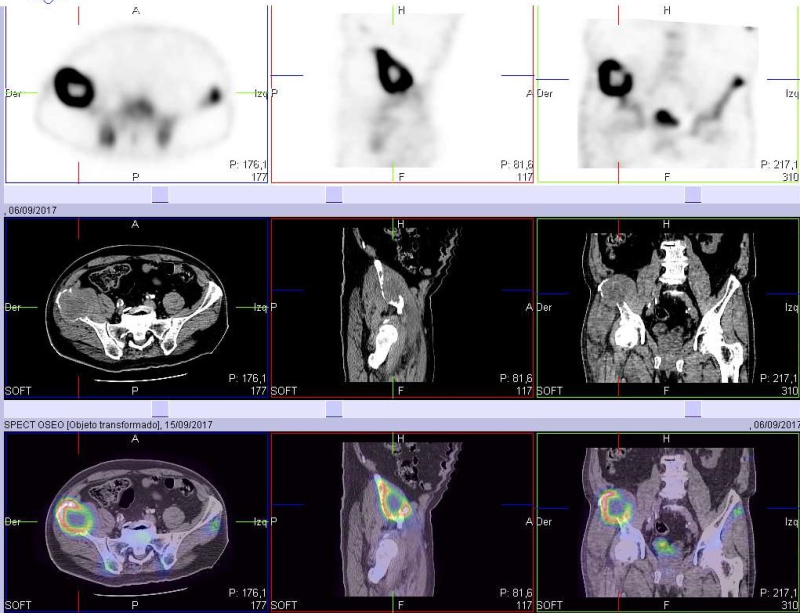

Se presenta el caso de un paciente masculino de 70 años con un único antecedente de carcinoma basocelular invasivo previamente operado, al cual le es solicitado un centellograma óseo debido a una lesión en alerón ilíaco derecho reportada en una tomografía computarizada (TC) de pelvis. Se realiza rastreo de cuerpo completo con 99mTc-MDP, imágenes estáticas de pelvis y SPECT. En el estudio de cuerpo completo se observó lesión en cresta ilíaca derecha, hipercaptante con componente lítico central, junto con un foco de hipercaptación de intensidad similar a la vejiga, proyectado por debajo de la rama superior del pubis derecho, de aspecto sacular (fig. 1). En las imágenes segmentarias con vistas anteroposteriores y laterales se evidencia que el hallazgo es de ubicación anterior respecto a la rama isquiopubiana derecha (fig. 2). En el estudio SPECT se confirma una gran lesión hipermetabólica con área central fotopénica de aspecto redondeado, que protruye de la cresta iliaca derecha y no respeta bordes anatómicos. Además, se evidencia claramente la existencia de conexión entre la vejiga y la zona hipercaptante de aspecto sacular ya mencionada (figs. 3 y 4).

Por estar disponible la TC de pelvis previamente realizada, se procedió a fusionar las imágenes (figs. 5 y 6) en las cuales se verifica conexión de la vejiga con una hernia inguinal (que no fue reportada en la TC) y la conocida lesión lítica en ala ilíaca derecha, con componente de partes blandas que se extiende al músculo ilíaco engrosado, sin reacción perióstica, característica de secundarismo. En una nueva TC en busca de la neoplasia primaria, se identifica una tumoración sólida en lóbulo superior del pulmón derecho, de aproximadamente 57 x 44 mm (fig. 7), sugestiva de carcinoma broncopulmonar (CBP).